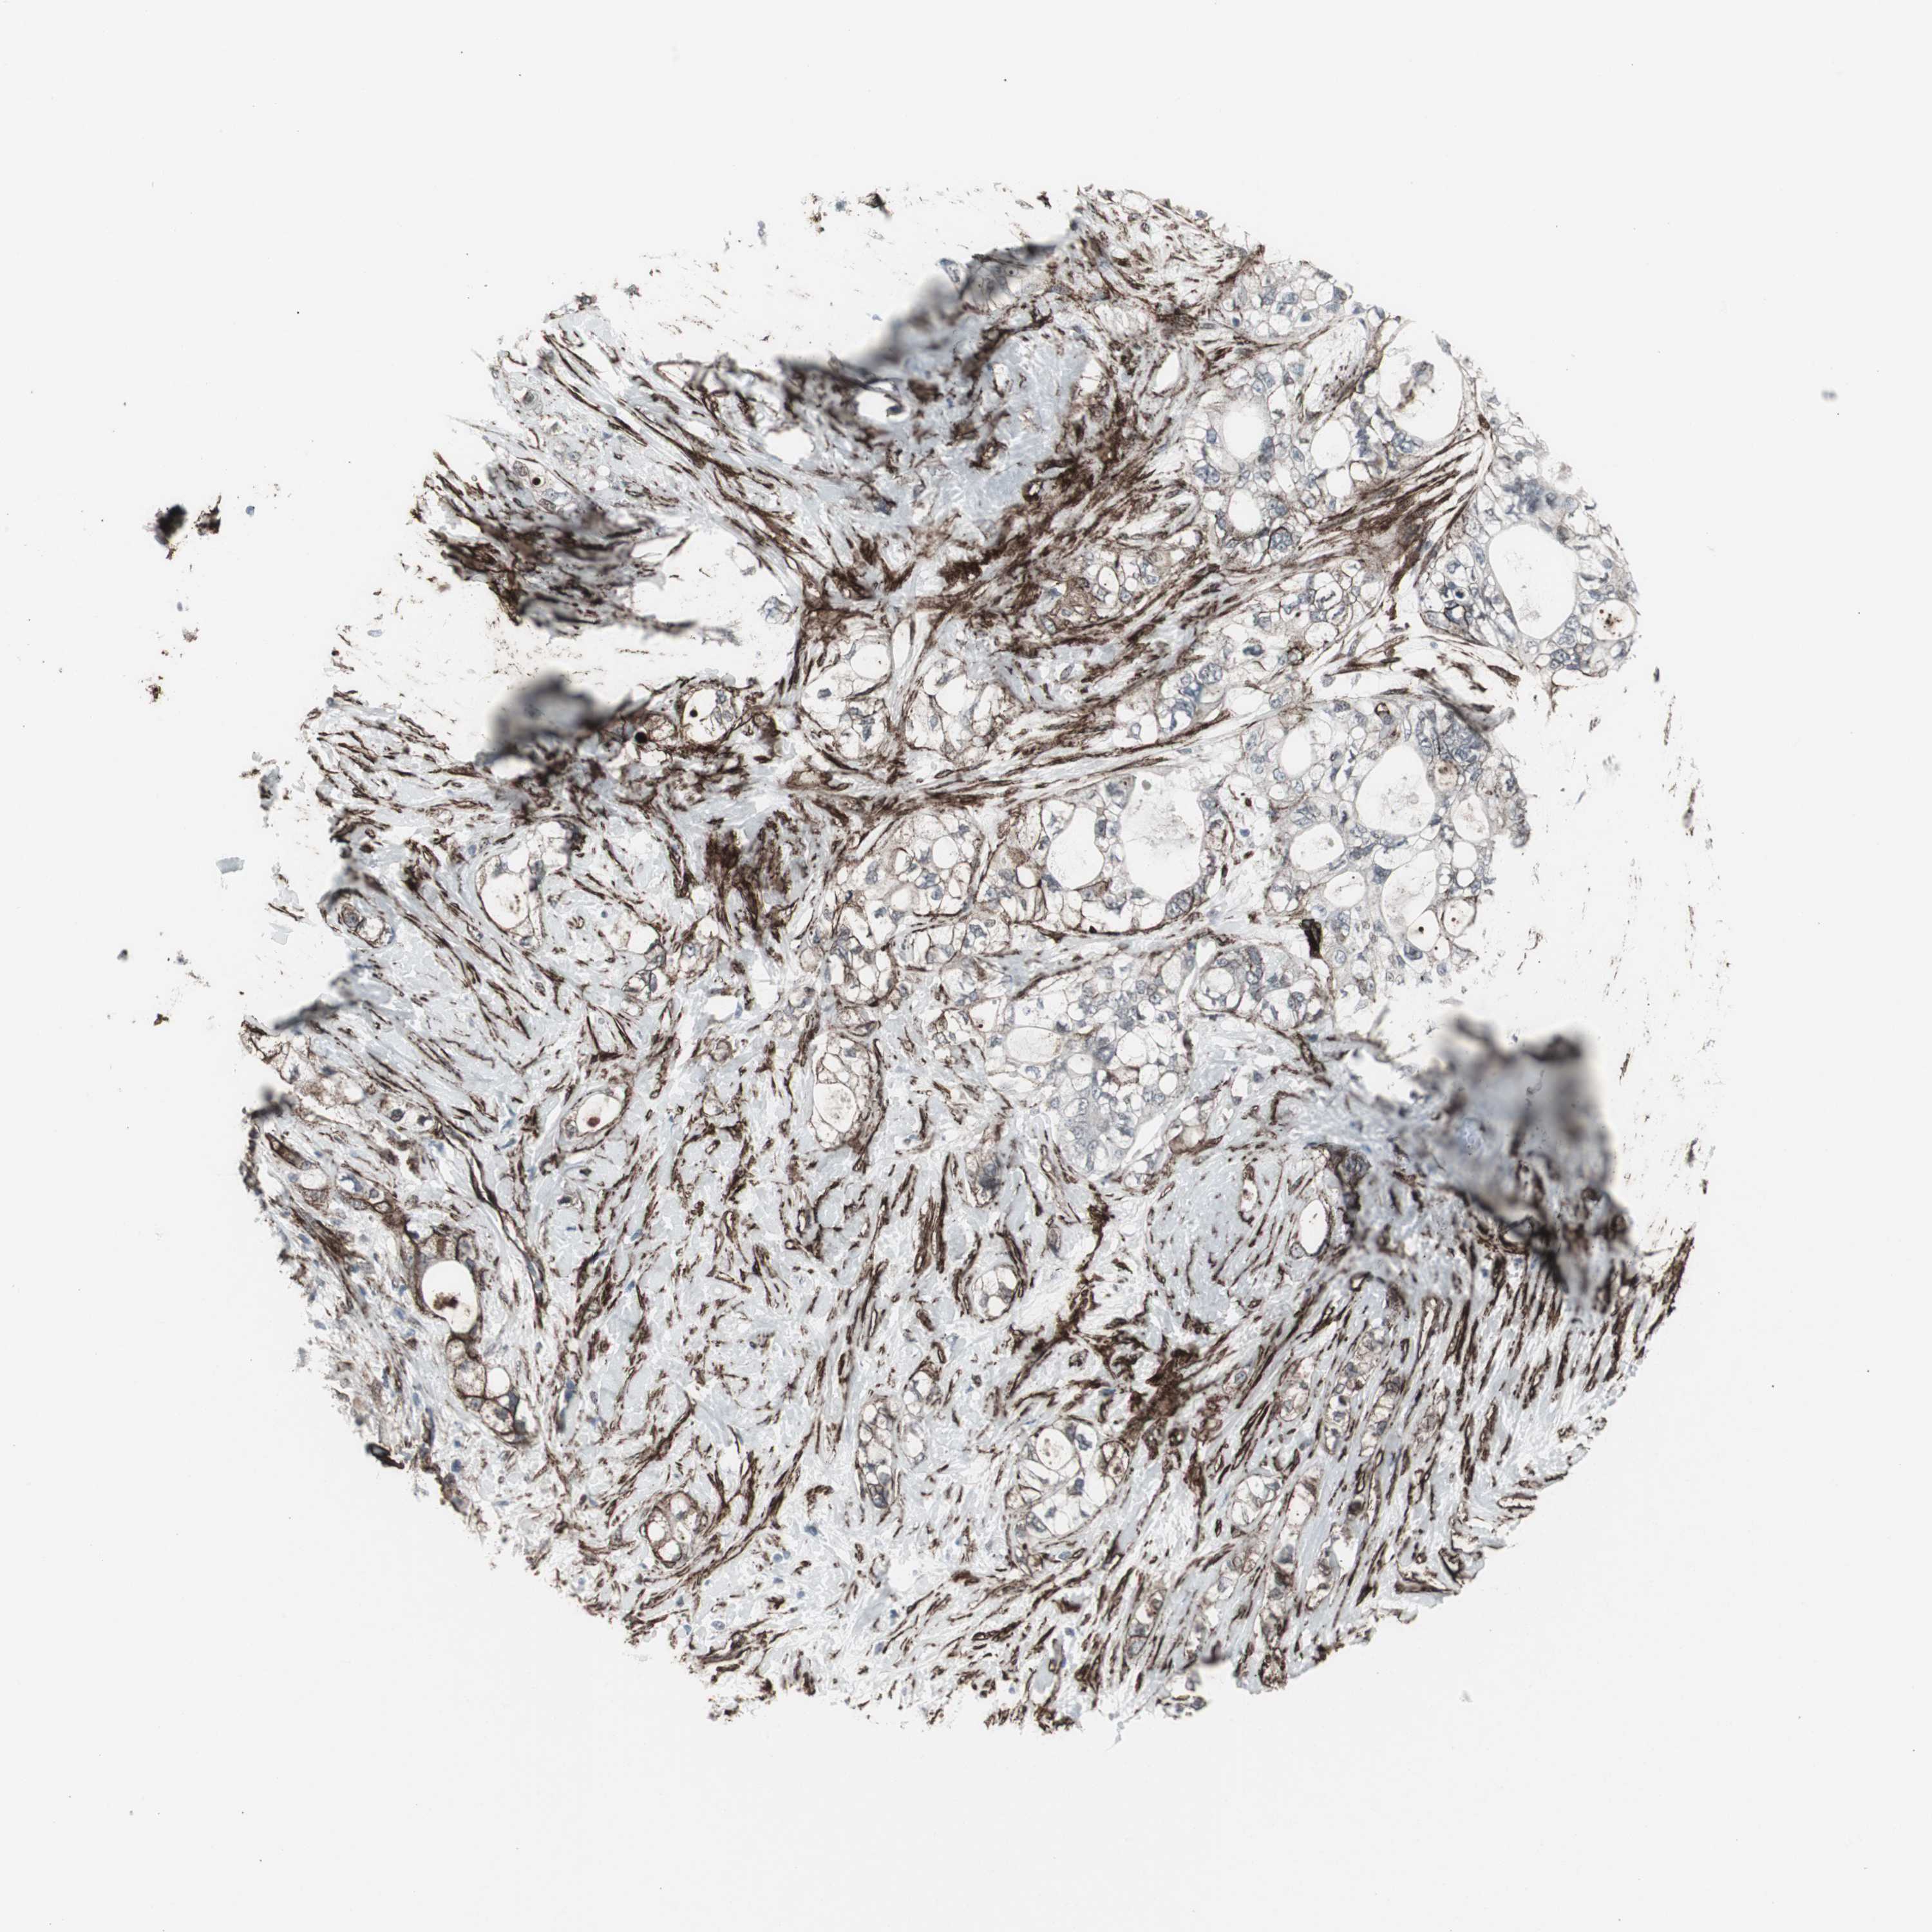

PANCREATIC CANCER - Protein expressioni

A mouse-over function shows sample information and annotation data. Click on an image to view it in a full screen mode. Samples can be filtered based on level of antibody staining by selecting one or several of the following categories: high, medium, low and not detected. The assay and annotation is described here.

Note that samples used for immunohistochemistry by the Human Protein Atlas do not correspond to samples in the TCGA dataset.

Antibody stainingi

Antibody staining in the annotated cell types in the current human tissue is reported as not detected, low, medium, or high, based on conventional immunohistochemistry profiling in selected tissues. This score is based on the combination of the staining intensity and fraction of stained cells.

Each image is clickable and will lead to virtual microscopy that enables deeper exploration of all samples and also displays staining intensity scores, fraction scores and subcellular localization as well as patient and tissue information for each sample.

Antibody CAB005579

Staining

High

Medium

Low

Not detected

Intensity

Strong

Moderate

Weak

Negative

Quantity

>75%

75%-25%

<25%

None

Location

Nuclear

Cytoplasmic/membranous

Cytoplasmic/membranous,nuclear

Adenocarcinoma, NOS

Adenocarcinoma, metastatic, NOS